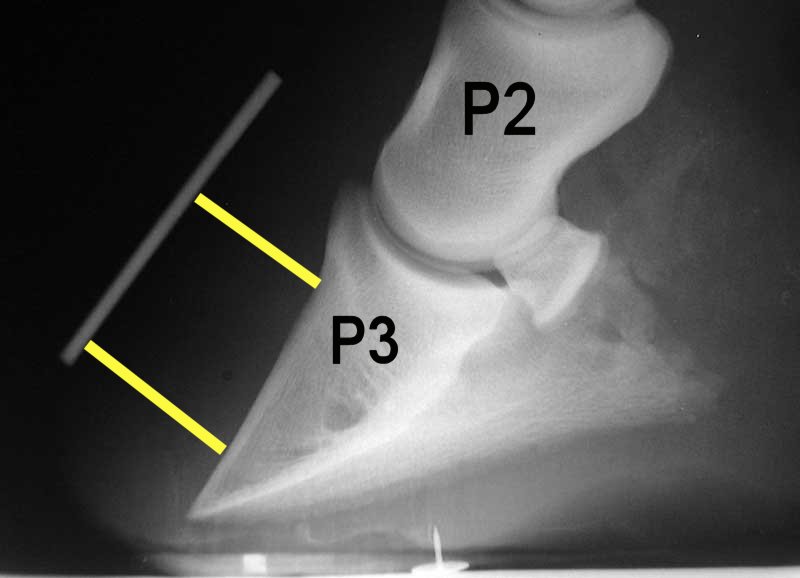

It’s vital for the hooves to be balanced and dressed to reduce the amount of damage that can occur. During the initial stages of the condition, the risk of the pedal bone in the hoof moving within the hoof capsule should always be of concern. As a result of the compromised structures within the hoof during an episode of laminitis, the pedal bone sometimes rotates within the foot and in more serious cases, can also sink downwards towards the sole.

If your farrier is asking for xrays then that’s a good sign for starters. It’s likely he’ll want to assess the position of the pedal bone relative to the hoof wall, solar surface and the point of the frog in a hope to trim the foot to help realign the angles relative to the position of the bone. This will be likely be done with consultation and input from the vet.

Most often than not in these cases, the trimming that is required when rotation has occurred involves the lowering of the heels and dressing of the dorsal (front) wall along with many of the elements of a regular trim for this pony. The amount of trimming will be indicated by what is shown by the xrays and the interpretation of what is ideal.

The vet will usually have placed markers on certain parts of the foot before xray to make it easier to assess the true point of frog, the angle of the outer wall and also the height of the coronary band so they can assess if the pedal bone has moved. These markers also make it easier to compare subsequent xrays at a later date.